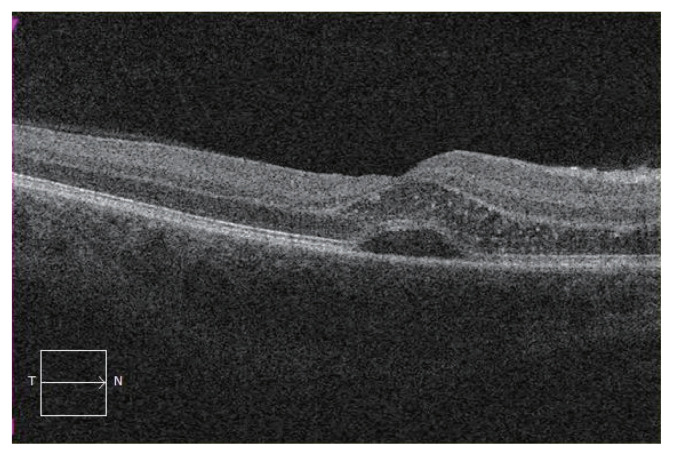

Results: Seventeen patients (19 eyes) were included with 11 (65%) being female. The mean age at presentation was 28.3 ± 12.3 years (range, 13-60 years). The mean presenting visual acuity (Early Treatment Diabetic Retinopathy Study testing) was 50 ± 23 (range, 4-90). The mean final visual acuity was 78 ± 12 (range, 45-90). Eleven patients (65%) had cats or kittens at home, with only one (6%) recounting a history of being scratched. Eight patients (47%) demonstrated the characteristic macular star at presentation, with all eventually developing macular star within a mean of 6 days. Four patients (24%) had macular oedema, three (18%) had vasculitis, two (12%) had uveitis, two (12%) had disc granuloma, and one (6%) had multifocal chorioretinitis. Six patients (35%) were treated with rifampicin and doxycycline, one (6%) with rifampicin and azithromycin, two (12%) with doxycycline only, two (12%) with co-trimoxazole monotherapy, and one patient (6%), who was breast-feeding, was treated with erythromycin. Four patients (24%) did not have receive any treatment.

Conclusions: The characteristic macular star is not always manifest at initial presentation for patients with neuroretinitis secondary to B. henselae, nor is there always a preceding history of cat exposure. Not all patients require treatment to have a good visual outcome, and the immune status of the patient is important.